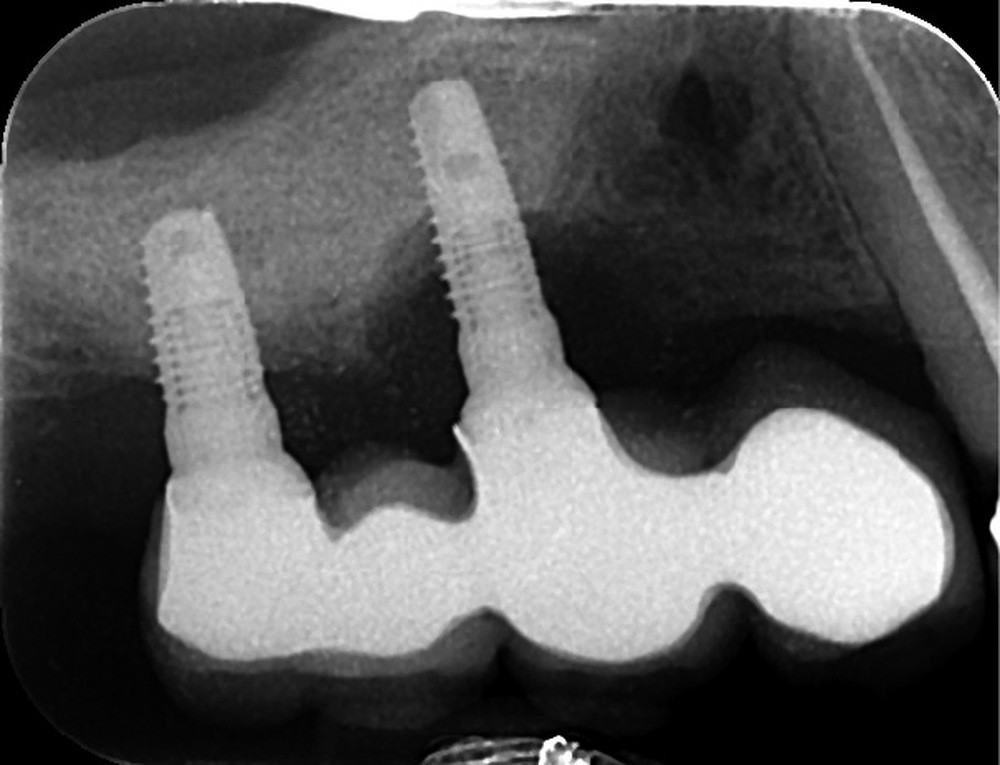

Le plus souvent pour des raisons carieuses et/ou parodontales l’avulsion d’une dent nécessite dans l’idéal son remplacement afin d’éviter une dégradation de l’appareil manducateur et des fonctions associées (mastication, phonation, sourire…).La mise en place d’implants dentaires ostéointégrés est une solution de choix pour remplacer les dents absentes car elle présente d’excellents résultats en termes de pérennité, de confort et d’esthétique. Ce n’est cependant pas une thérapeutique parfaitement fiable à 100 %. Dans un certain nombre de cas, des pertes osseuses péri implantaires se produisent, pouvant entraîner un inconfort, des douleurs et parfois la perte des implants.

Jemt [1] a listé de manière exhaustive les facteurs pouvant être responsables de la perte osseuse autour des implants (fig. 1). Il en a recensé au total 86. Cela montre bien l’origine plurifactorielle de ce type de pathologie. Il est difficile de traiter ici tous ces items ; cet article s’intéressera à deux grands types de facteurs de risques : l’hygiène bucco-dentaire (Jemt cite les antécédents de maladie parodontale, les causes de la perte des dents, le tartre, le biofilm, la plaque, le génotype et le phénotype bactérien) et la prothèse supra-implantaire (le design de l’infrastructure, son adaptation, son immobilité, le design de la prothèse sont également listés).